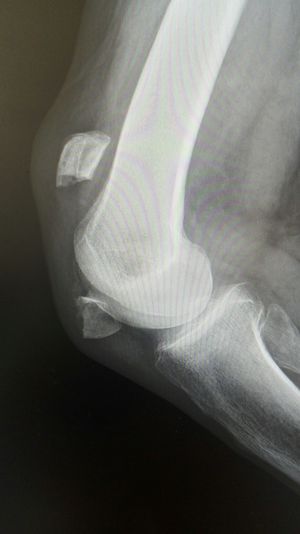

Xray

Fracture

Patella